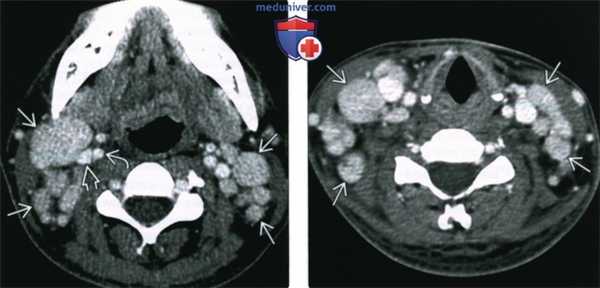

(Слева) КТ с КУ, аксиальная проекция. Девушка с выраженной двусторонней шейной аденопатией. Определяются множественные шейные лимфоузлы различного диаметра, контраст накапливается также интенсивно, как и в соседних внутренней сонной артерии и внутренней яремной вене.

(Справа) КТ с КУ, аксиальная проекция, эта же пациентка. Признаки аденопатии без некроза, кальцификатов или воспаления окружающей клетчатки. После биопсии был выставлен диагноз смешанной гиалиново-васкулярной и плазмоцитарной болезни Кастлемана. Это наиболее редкая форма заболевания.

(Слева) ПЭТ в аксиальной проекции, выполненная через два дня после КТ, эта же пациентка. Умеренное накопление ФДГ в узлах шеи.

(Справа) ПЭТ в прямой проекции, эта же пациентка. Других очагов захвата ФДГ на теле нет, умеренный захват ФДГ на шее. Функция почек в норме.